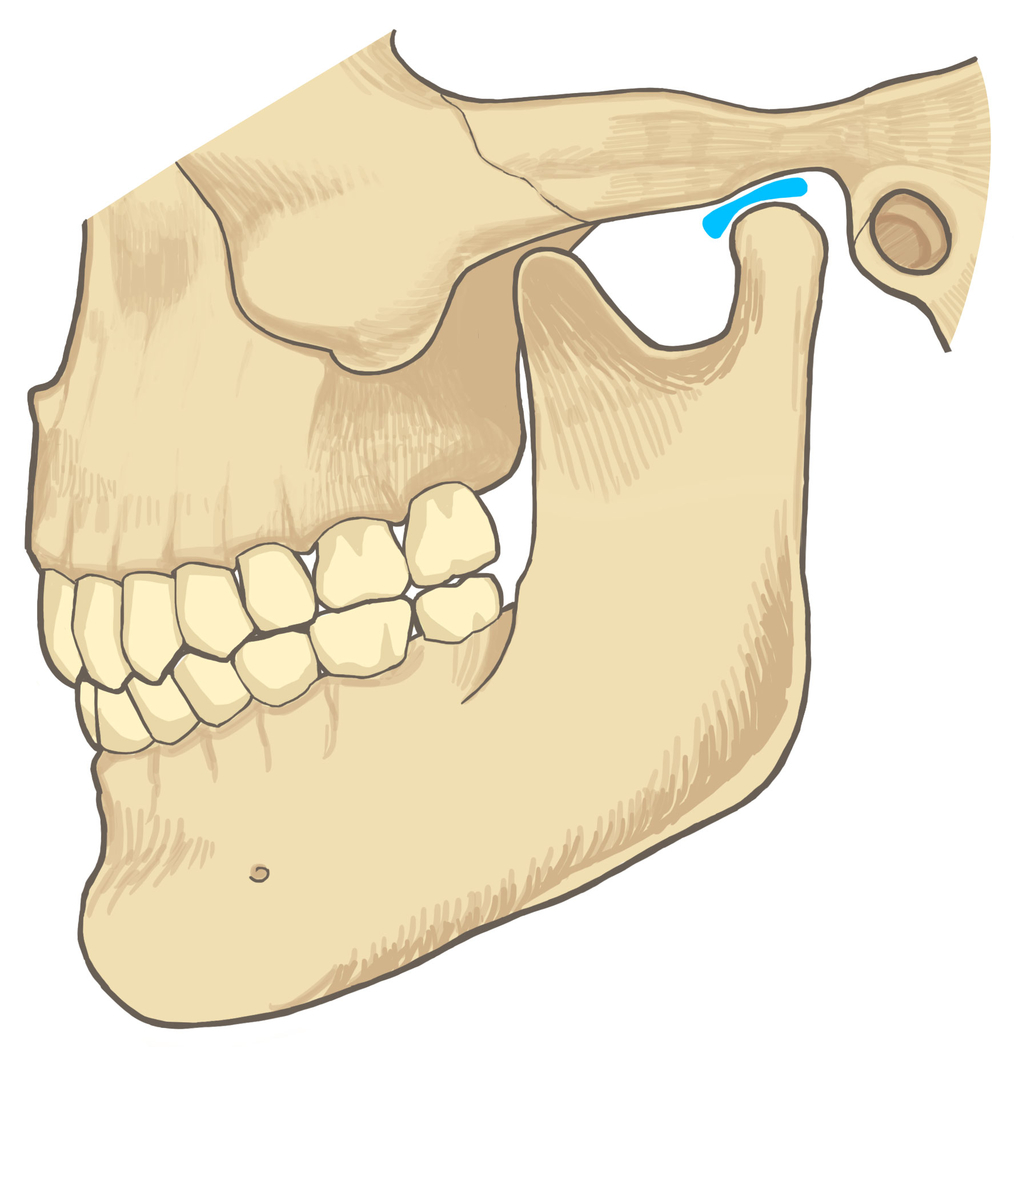

顎関節とは

顎関節とは、耳の少し前あたりにある頭蓋骨と下顎のつなぎ目のことを言います。

上顎は頭蓋骨にくっついていて動かすことはできないようになってます。

下顎は独立した骨になっていて、筋肉でぶら下がっているような形でくっついている状態です。

なので、下顎はいろんな方向に動かせますよね?

固定されている上顎と自由に動く下顎をつなげているのが顎関節と呼ばれるものになります。

その間に挟まれている軟骨を関節円板といいます。

この関節円板の動きが妨げられるとガクッと音が鳴ります。